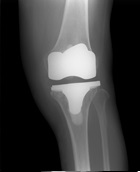

3.画像診断

- X-P所見(別紙参照):FTA左167°

- 骨折の特徴や手術法の特徴などを理解した上で、治療手技を考えていく必要がある。主なリスクは担当医に確認する

| 術前 | 術後 | 経過 |

![]() |

| FTA | 大腿骨と脛骨の長軸のなす大腿脛骨角。正常は約176度 |

| Mikulicz線 | 大腿骨頭中心から足関節中心を結ぶ下肢機能軸は立位での下肢荷重線を表し、正常では膝関節のほぼ中央を通過する |